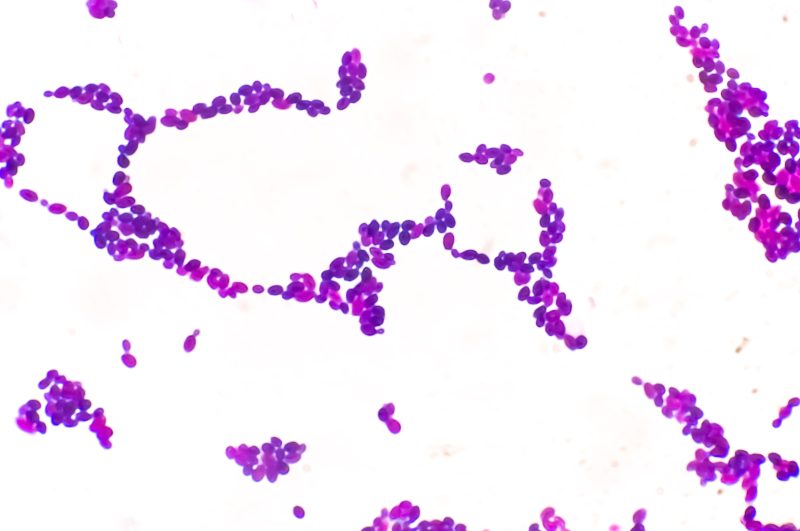

Drug-resistant fungus Candida auris identified in 17 states

The bacteria Candida Auris, known for its resistance, is being closely monitored by health experts working to control its spread. This fungus was first identified in the U.S. about ten years ago, and since then, the number of reported cases has risen each year. According to data from the Centers for Disease Control and Prevention […]